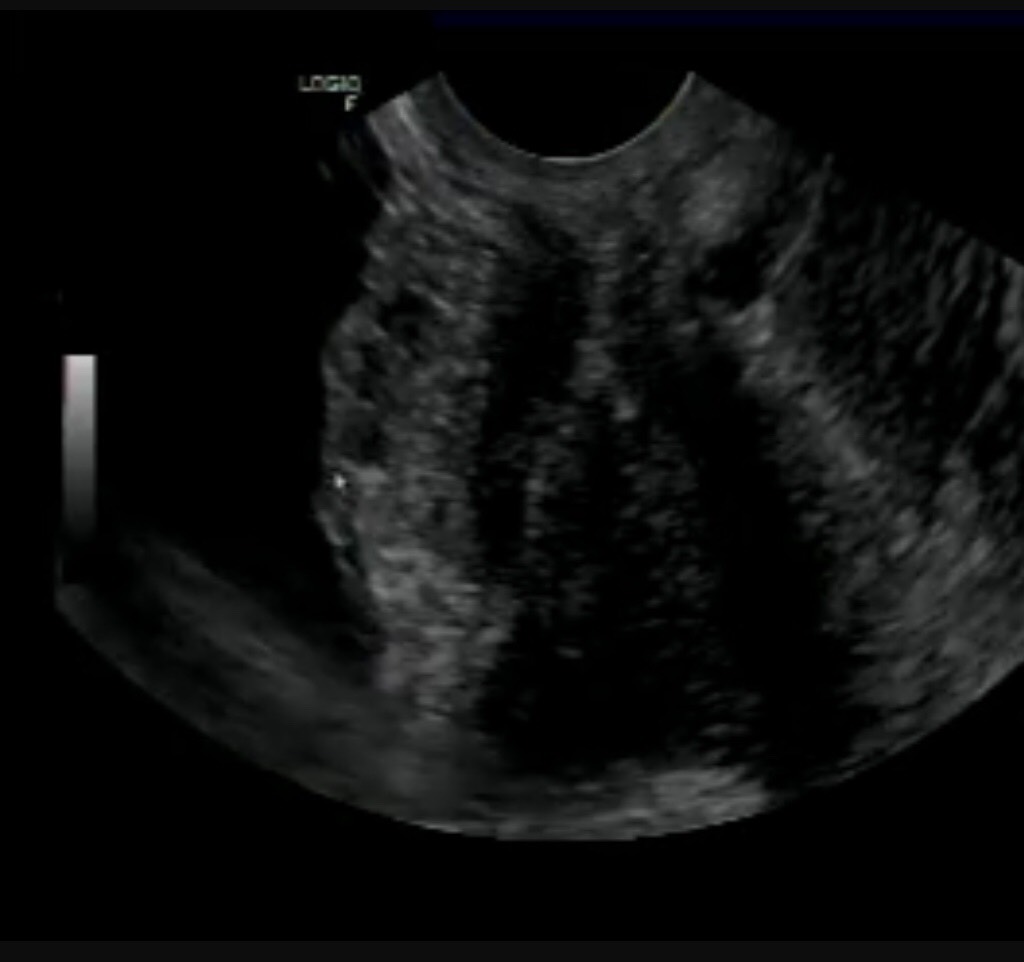

Kết quả siêu âm của bệnh nhân, Siêu âm qua đường bụng và đầudò qua ngả âm đạo :Ghi nhận cấu trúc echo kém kích thước # 38 x 19mm ở cùng đồ trước, giới phía trước tử cung-sau bàng quang, đẩy lồi vào lòng bàng quang, giới hạn khá rõ, bờ kém đều, bên trong có nhiều nang nhỏ, xâm lấn làm mất cấu trúc lớp thành sau bàng quang, thành trong bàng quang vẫn còn khá mịn màng.

Từ triệu chứng lâm sàng + hình ảnh siêu âm chúng tôi chẩn đoán : Lạc nội mạc tử cung ở thành sau bàng quang – Bladder endometriosis.